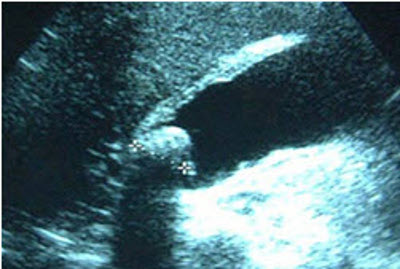

Gravidez ectópica: imagem de ultrassonografia de gravidez ectópica mostrando o sinal de "donut"

Do acervo pessoal de Dra. Melissa Fries, Washington Hospital Center; usado com permissão

Gravidez ectópica: imagem de ultrassonografia de gravidez ectópica